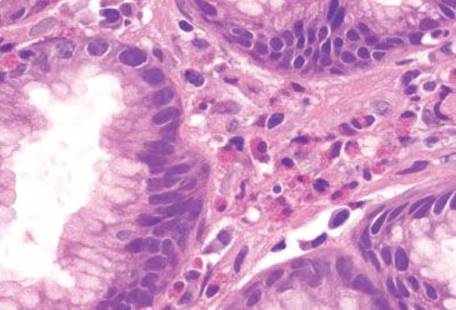

Figure 2.156 Gastric mucosal eosinophilia pattern. Increased numbers of eosinophils are present in the lamina propria of this gastric biopsy. An etiology for this finding was not apparent, and a list of differential diagnoses was given to aid in clinical correlation.